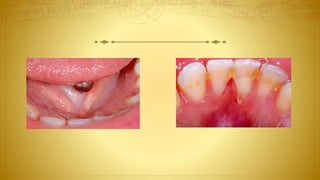

• Aberrant frenal insertions: Ankyloglossia? Blanching?

• Oral hygiene-induced or self-induced lesions

–– Stilman’s clefts? Incomplete (red) or complete (white) lesions

–– McCall’s festoons

–– Gingival erosion